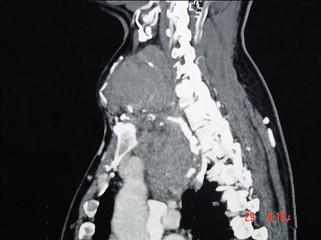

问题 女性,48岁,颈部包块3年,近来胸闷、憋气、胸痛,CT扫描如图,请选择正确的描述和答案 ( )

选项 A、胸骨后甲状腺肿是指甲状腺50%位于胸骨后 B、胸骨后甲状腺肿是指甲状腺60%位于胸骨后 C、考虑为血管瘤 D、考虑为双侧甲状腺肿大 E、考虑为胸骨后甲状腺肿

答案 AE